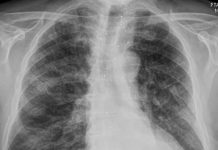

70 year-old male patient presented to the ED with fever for 10 days, occurred after exposure to a Covid-19 patient. No dyspnea neither cough. pO2: 95%. Medical history: chronic thyroiditis, HTA.

Portable chest film (performed in a tent set up outside the ED):

diffuse interstitial markings w/o alveolar consolidations.

Multiple and bilateral ground-glass opacities with predominant subpleural distribution in the upper lobes, in the ML and in the lower lobes. The findings were consistent with COvid-19 pneumonia.

The RT-PCR test on nasopharyngeal swab turned positive.